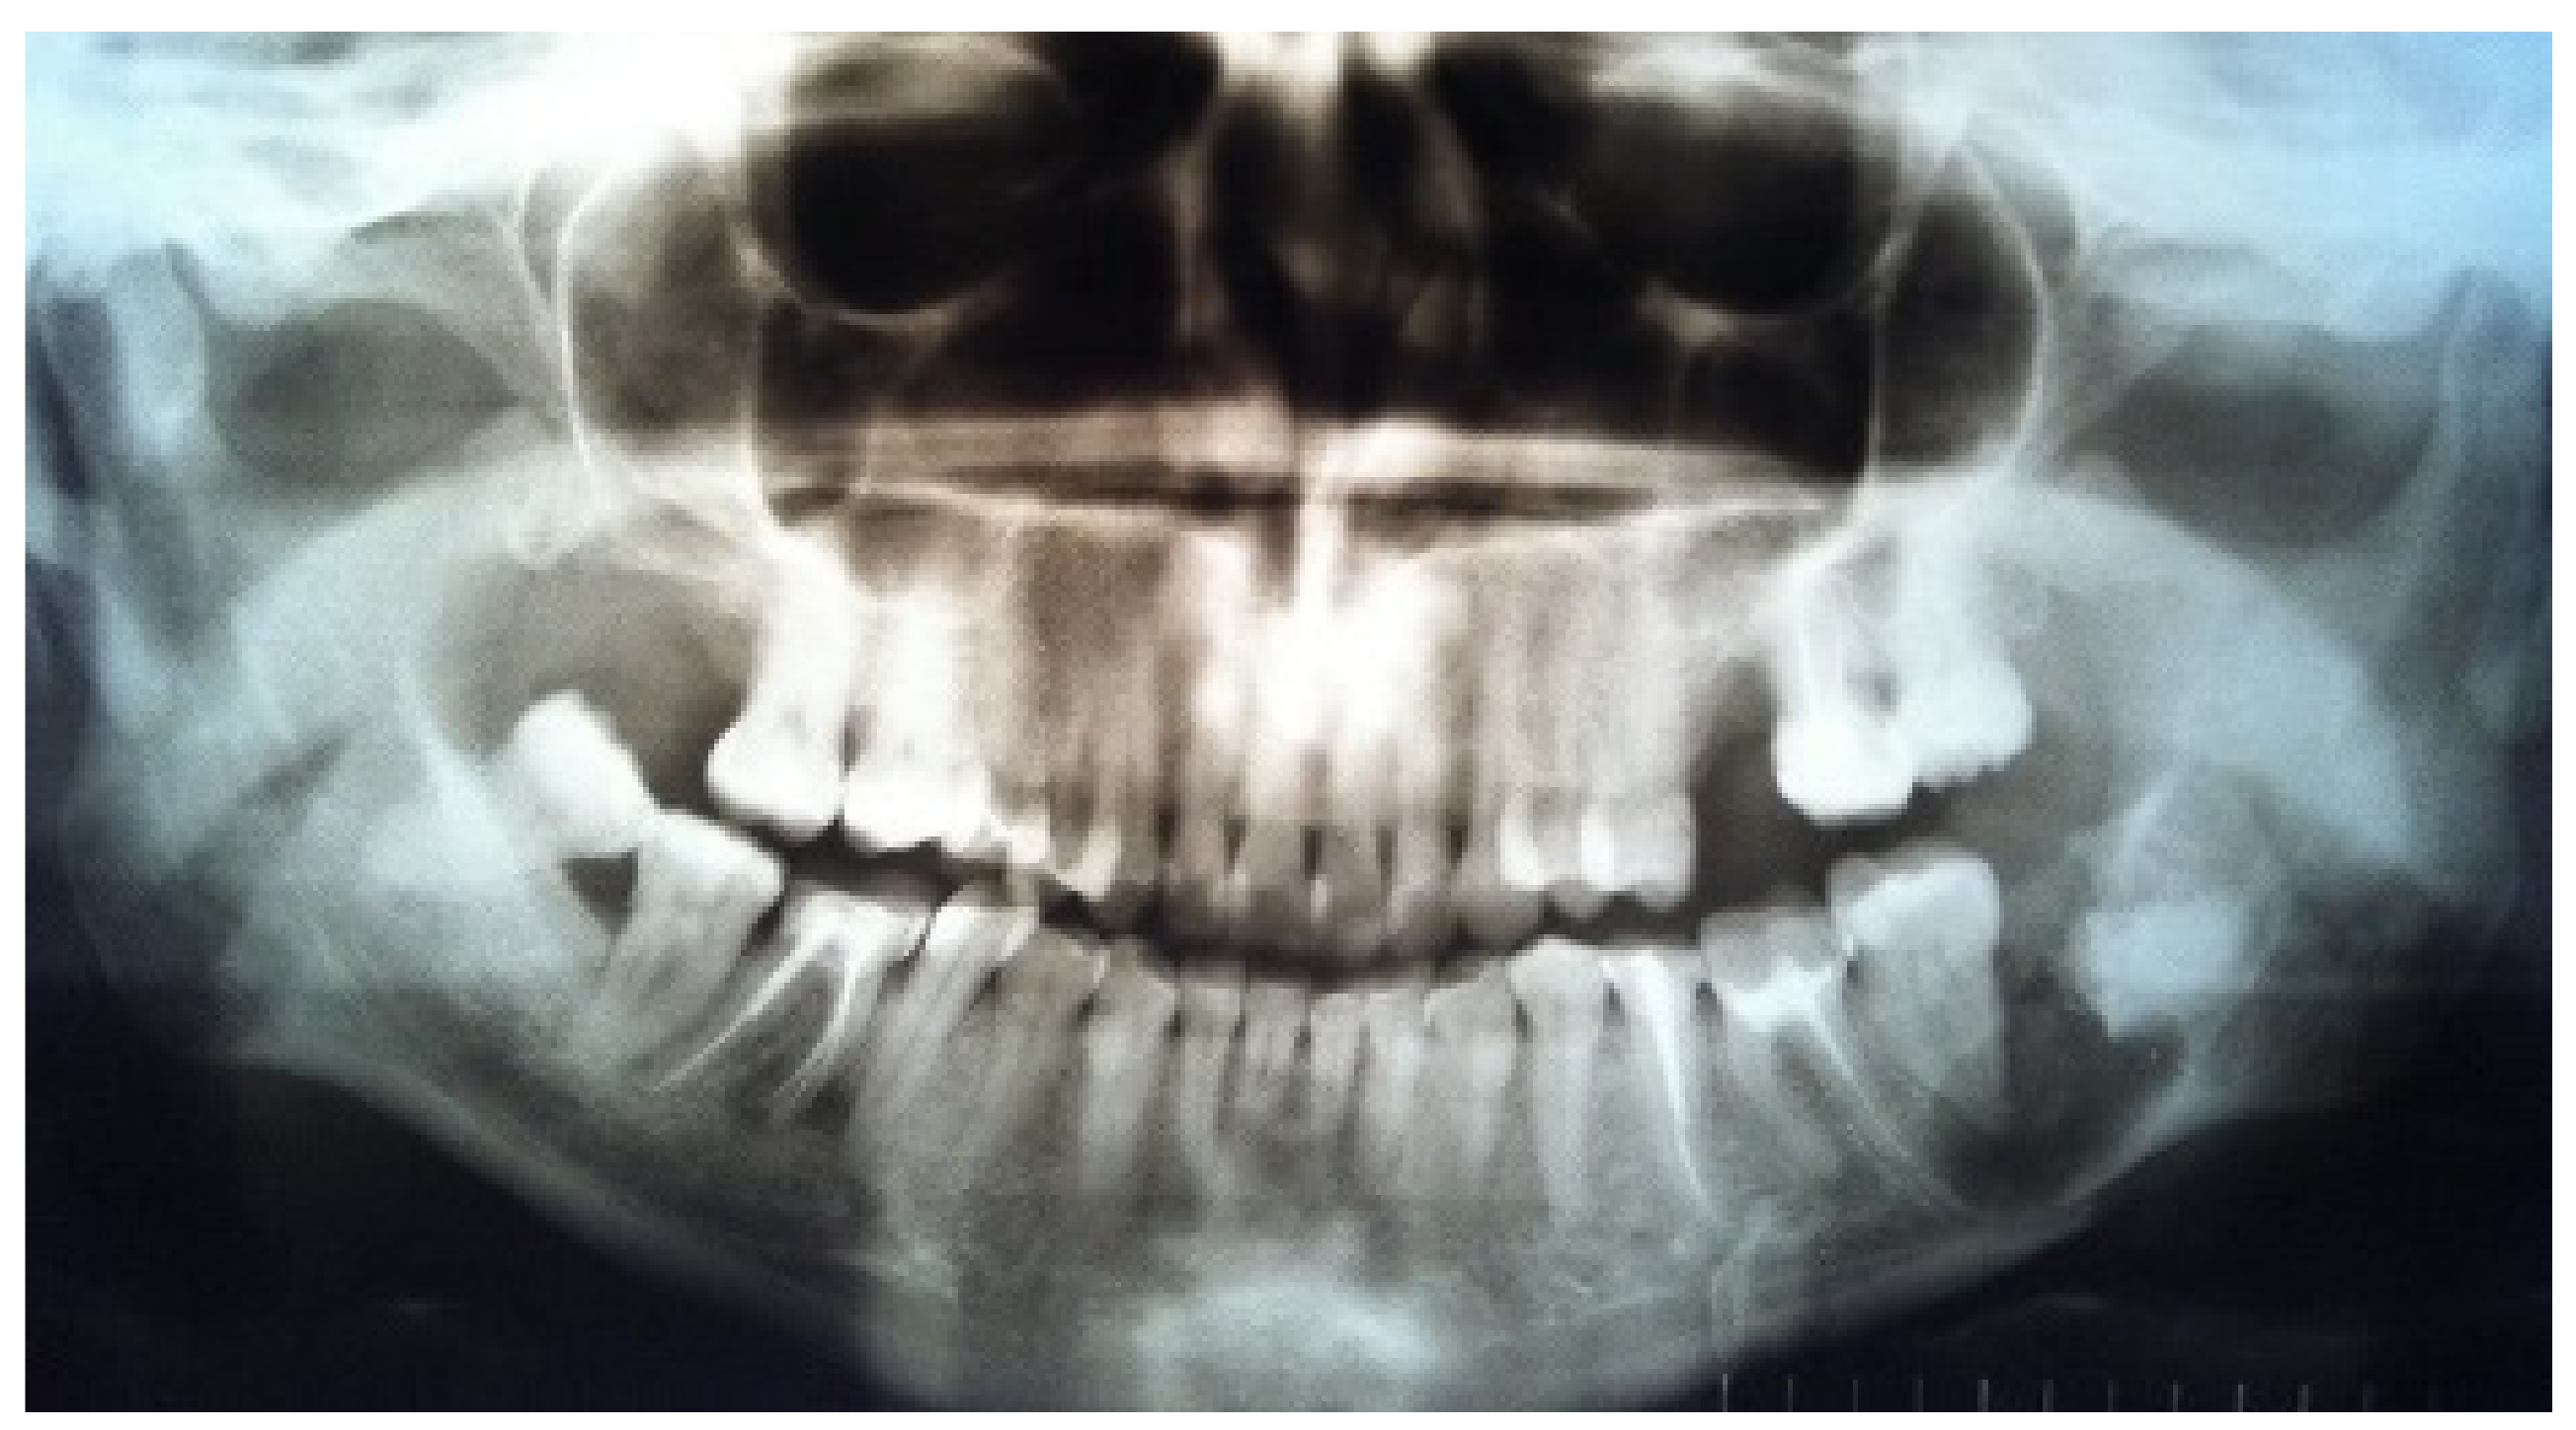

The orthopantomogram showed a fracture line in the area of tooth 3.8 and an oval-shaped area of radiolucency with teeth 3.7 and 3.8, with root involvement (Figure 1).

Figure 1.

Orthopantomogram before surgery.